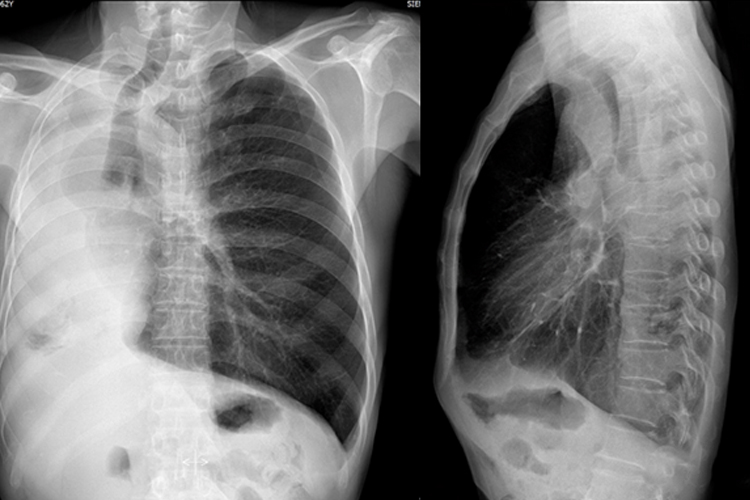

一侧肺不张

一侧肺不张X线表现为患侧肺野呈均匀一致性的密度增高影,胸廓塌陷,肋间隙变窄,纵隔向患侧移位,横膈升高,心缘及横膈影均不清楚,健侧肺呈代偿性肺气肿表现。